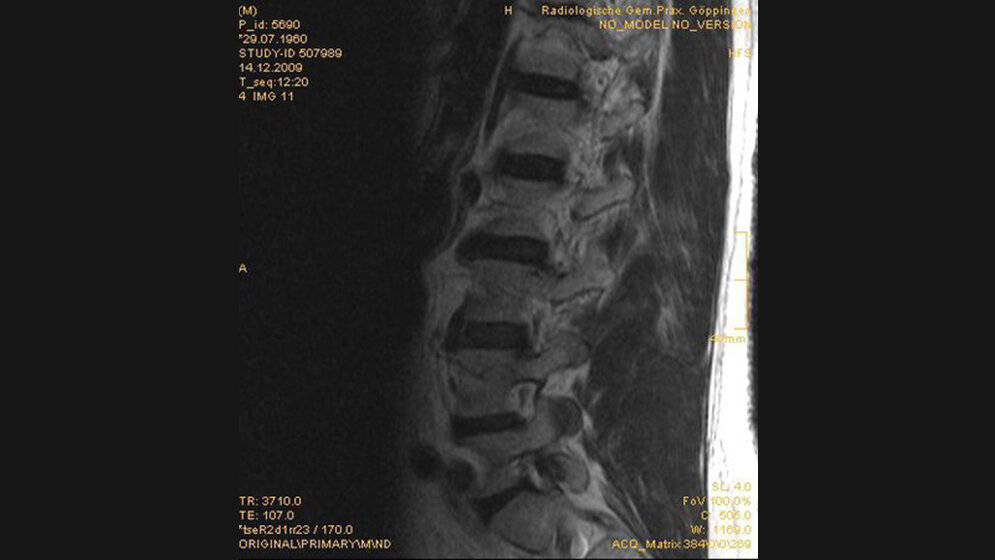

Abdominelle Aortenaneurysmen kommen in einem kleinen Bevölkerungsteil vor und sind durch eine zunehmende Aortendilatation mit unvorhersehbarem zeitlichen Verlauf charakterisiert. Inzidentale Aortenaneurysmen kommen relativ häufig vor und werden selten erfasst. Das Monitoring ist wichtig und hat einen bedeutenden Einfluss zur Vermeidung der Aortenruptur mit tödlichem Verlauf.